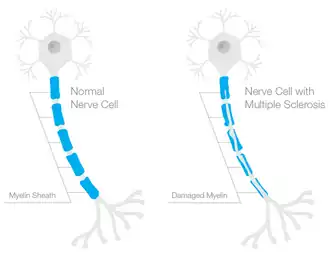

A neurodegenerative disease is a disease that causes damage to neurons. Examples of neurodegenerative disease include Alzheimer's disease,[14] Parkinson's disease,[15] and amyotrophic lateral sclerosis.[16] For example, multiple sclerosis (MS) is an inflammatory neurodegenerative disease where the body initiate an inflammatory reaction in the central nervous system, and causes damage to neurons.[17][18] Neurodegeneration is different in each disease; for example, MS is a result of a degenerative process called demyelination.[17] On the other hand, Parkinson's disease results from damage of neurons in the Substantia Nigra, which is important to initiate motor behavior.[19]